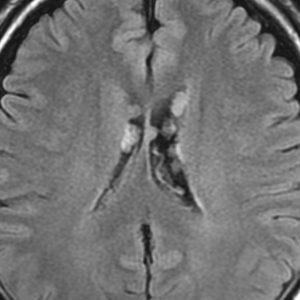

よくみつかる典型的な例です

中年男性に偶然発見された15mmくらいの上衣下腫です。側脳室前角の壁にピッタリくっつくようにキノコのように生えています。下の2枚はガドリニウム造影ですが増強されないのが特徴です。この点で中枢性神経細胞腫 central neurocytomaと区別できます。中枢性神経細胞腫はゆっくりですが大きくなる腫瘍です。でもこのような上衣下腫は大きくなるのはとてもまれです。小さいし水頭症にもならないので,なにも治療しないでほっておきます。間違っても開頭手術などしません。